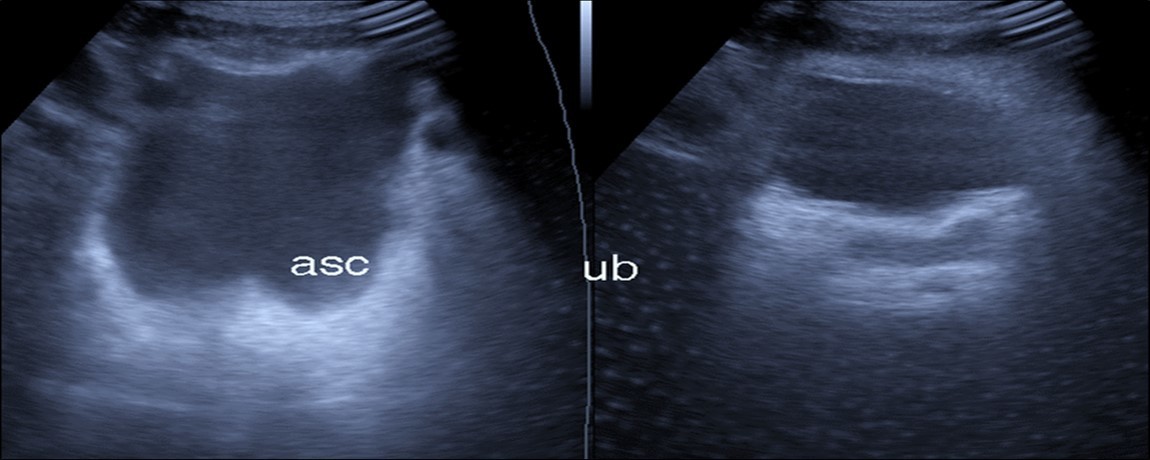

Abdominal ultrasound may revealed any of the followings:-Mild hepatomegaly with echogenic parenchyma and ascites in cases with hepatic impairment (Figure 4, Figure 5) ,thick walls of gall bladder with mildly dilated Common bile duct suggesting of biliary stasis and cholecystitis (Figure 6) .Abnormal renal echogenicity (Figure 7), suprarenal gland enlargements with heterogeneous texture ,splenic wedge shape area of hypoechogenicity ,thickened walls of bowel mainly the rectosigmoid region ,dilated bowel loops with free peritoneal fluid, and gases in the bowel wall with mesenteric and portal vein gases suggesting of bowel wall infarction13.

Figure 6.Real time ultrasound showing free ascites (asc) in patient with Covid-19.